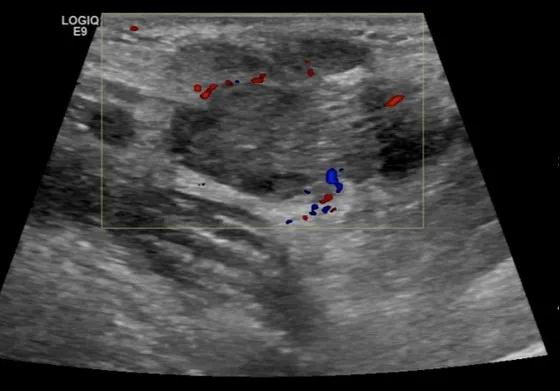

第三例是甲状腺癌患者,双侧甲状腺癌切除术后、碘治疗后一年余效果欠佳,超声显示左颈3区3枚低回声结节,穿刺示甲状腺乳头状癌转移。患者不愿意手术,希望采取局部治疗。对病灶进行液体隔离后采取热消融术,由于淋巴结较小,热消融一分钟左右完全灭活,术后增强影像显示没有脏器充填。

(病例3图例)